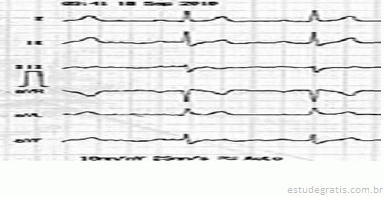

Paciente, sexo masculino, 45 anos de idade, sem patologia

Paciente, sexo masculino, 45 anos de idade, sem patologias prévias, totalmente assintomático, sem histórico familiar positivo para quaisquer patologias cardiovasculares, foi ao médico, pois estava com uma hérnia inguinal. Seu médico solicitou um eletrocardiograma, apresentado em seguida.

Com base nesse caso clínico, e considerando os conhecimentos médicos a ele relacionados, julgue os itens a seguir.

A cirurgia deve ser suspensa até esclarecimento correto do diagnóstico.Comentários